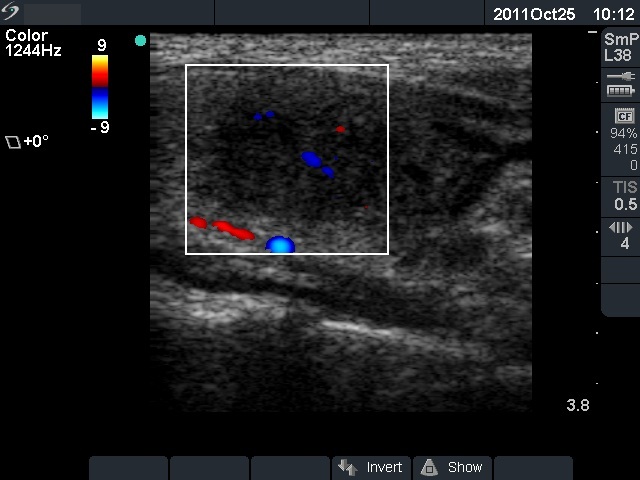

Initial examination (first row of images):

Ultrasonography: The right thyroid was echonormal and contained several small, insignificant lesions. There was a hypoechogenic lesion with blurred borders in the central and in the ventro-medial part of the left thyroid with increased intranodular blood flow.

The ultrasound pattern of de Quervain's thyroiditis and that of papillary cancer are very similar: a hypoechogenic lesion with blurred borders are found in both cases. They differ in vascularization statistically but the vascular pattern has only limited practical significance. In the acute phase of de Quervain's thyroiditis the vascularization is generally decreased but even in this case the situation was the opposite. The finding of not one but multiple hypoechogenic areas favored the possibility of subacute thyroiditis.